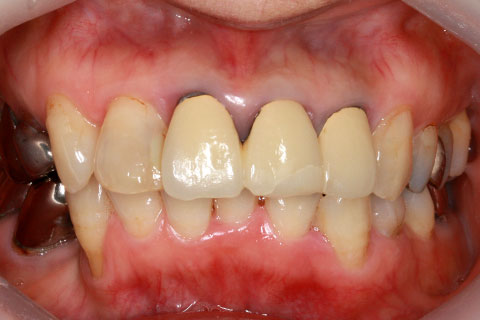

• オールセラミックの症例2

治療前

治療後

年齢・性別

45歳男性

治療期間

2ヶ月

抜歯

なし

治療費

70.4万円

備考

前歯8本の歯列不正によるセラミック治療

治療内容

歯質を削除し、セラミック冠をセメント合着

施術の副作用(リスク)

知覚過敏、歯髄炎、荷重負担